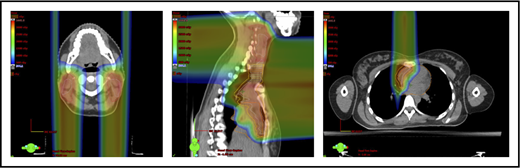

With regard to field arrangements, the PBSPT technique for an anterior upper mediastinal and lower neck target usually requires 1 (repainted) or 2 anterior fields. For more complex target volumes, targets can be divided into 2 or more parts (eg, neck CTV, mediastinal CTV, and axillary CTV), and a multifield plan can be used (Figure 5). For cases that involve lower (posterior) and upper (anterior) mediastinal targets, a combination of posterior and anterior fields can maximally spare the heart and lungs (Figure 6). For upper neck targets, lateral or posterior fields can avoid the oral cavity/salivary structures. For axillary targets, a posterior field can help to spare breast tissue. Although these various field arrangements can be used in PSPT, gradient matching is simpler in PBSPT when the fields overlap or oppose, obviating the need for feathering.

Plans for PBSPT with a single-field uniform dose and a gradient match, with anterior and posterior beams used to treat disease that involves the bilateral upper neck and the mediastinum (disease anterior to the right heart).

Scans for a young woman in whom the target included mediastinal, left parasternal, and left axillary regions. One anterior field was used for the mediastinum, and a separate posterior field was used for the axillary region.